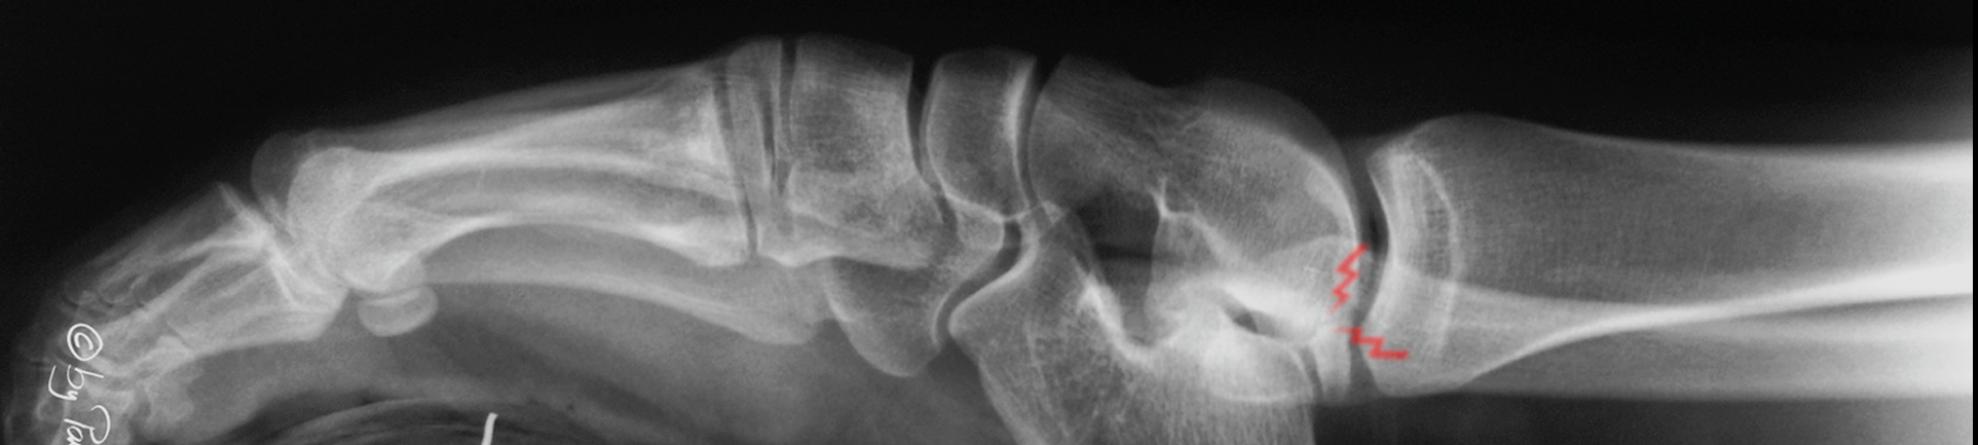

Full medial facet subtalar coalition

20 year old woman